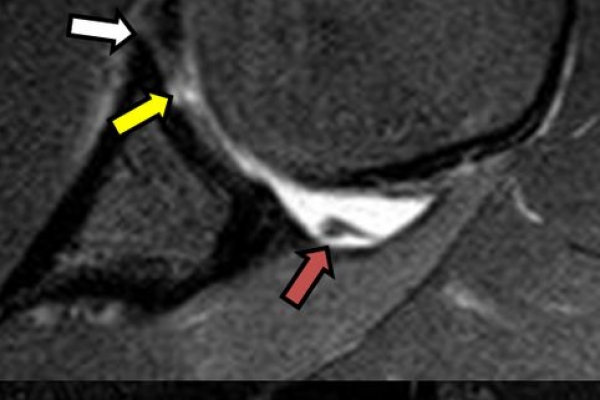

Είναι μια ελάχιστα επεμβατική απεικονιστική μέθοδος που επιτρέπει τη λεπτομερέστερη διερεύνηση του εσωτερικού των αρθρώσεων. Η ασφαλής έγχυση σκιαγραφικού εντός της άρθρωσης υπό ακτινολογική καθοδήγηση και η ακόλουθη απεικόνιση της άρθρωσης με αξονική ή μαγνητική τομογραφία (ή και με συνδυασμό των μεθόδων) αποσαφηνίζει βλάβες του χόνδρου και κακώσεις-ρήξεις συνδέσμων και τενόντων με υψηλή ακρίβεια, συμβάλλοντας σημαντικά στο λεπτομερή χειρουργικό σχεδιασμό.